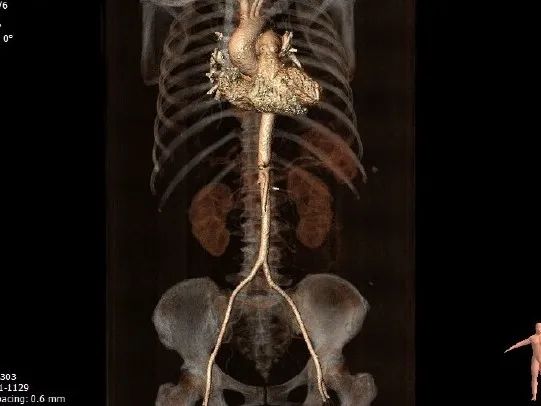

CT测量

瓣环周长:67.2mm

LVOT周长:67.5mm

瓣环上4mm:66.3mm

瓣环上6mm:65.4mm

左冠开口高度:13.2mm

右冠开口高度:11.7mm

瓣环角度:59°

升主动脉周长:109.9mm

主动脉瓣钙化情况

入路情况